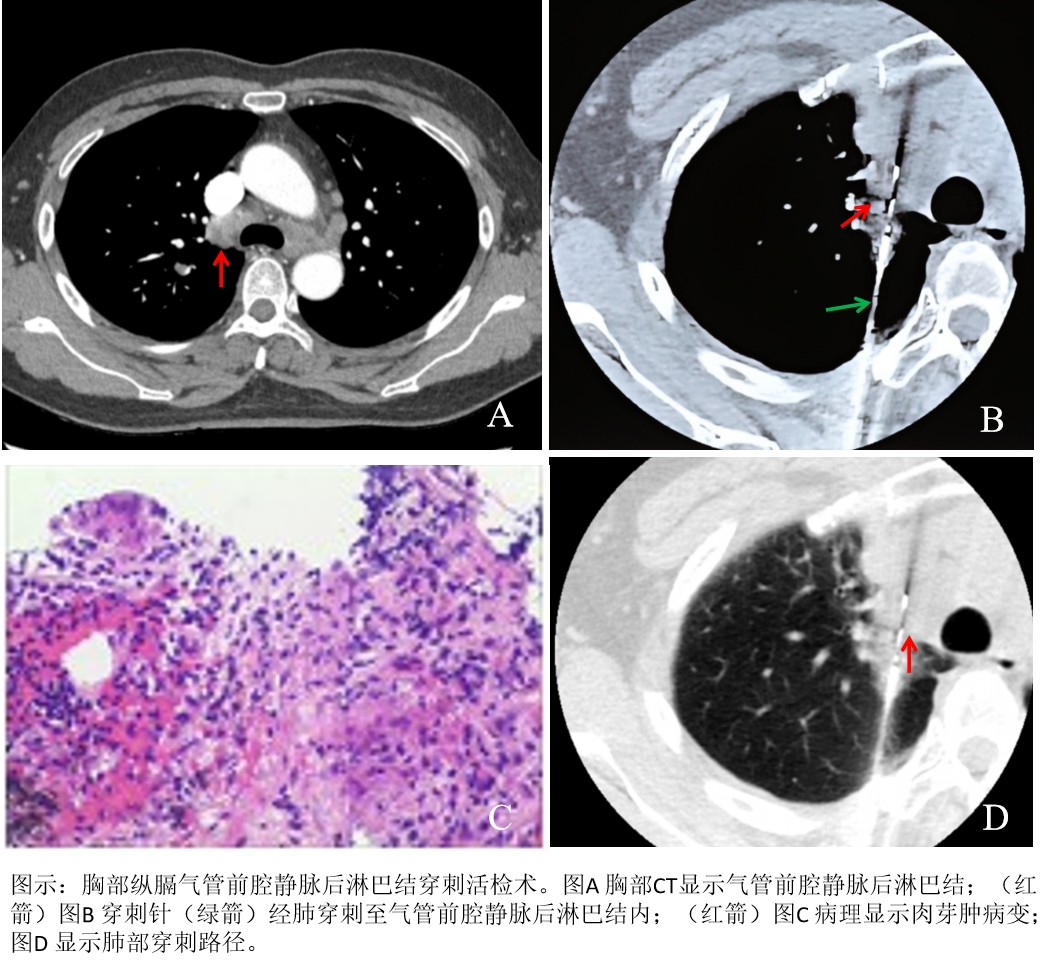

为破解诊断难题,经多学科会诊(MDT)讨论,医院决定依托放射科介入团队的技术优势,采用CT引导下经皮纵隔淋巴结穿刺活检术获取病理组织。为确保手术万无一失,放射科团队术前反复研究患者影像学资料,精准规划穿刺路径,避开血管、气管等关键结构,制定了详细的手术方案与应急预案。

手术当天,通过CT动态扫描实时定位,手术团队精准把控进针角度、深度,成功取得足量纵隔淋巴结组织标本。整个操作过程仅用时30分钟,患者无明显不适,术后生命体征平稳,未出现气胸、出血等并发症。

术后病理结果很快出具,最终确诊患者纵隔淋巴结肿大为肉芽肿性病变,而非子宫内膜癌转移。这一结果彻底改变了患者的后续治疗方案,避免了不必要的放化疗,为患者制定个体化治疗方案提供了“金标准”依据。目前患者已进入对应的治疗阶段,恢复情况良好。